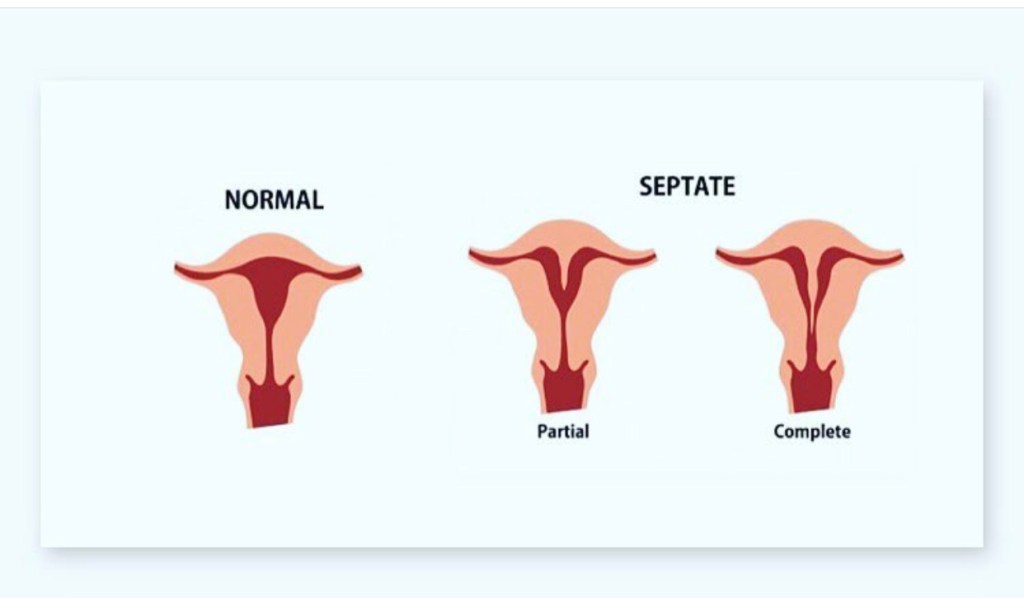

At the appointment, the doctor identified that I have a uterine abnormality. She explained that a uterus is supposed to be pear shaped but mine was shaped like a heart. There is a septate wall that is in the middle of the uterus that makes it look like a heart. This wall is fibrous and doesn’t have blood flow and is not strong enough to hold a baby if the embryo attaches to it. She explained that although there are many reasons miscarriages happen, some of which are unexplained, having a septate uterus meant, I have a higher chance of miscarriage, not just in the first trimester but a higher chance of a 2nd trimester miscarriage. I also have a 90% of pre term labor which means my baby would be premature and I would have to have a c section because there wouldn’t be enough space for the baby to turn.

Wow, I had no idea. I knew I had a heart shaped uterus but I thought that just meant more painful periods. I never thought it would affect my pregnancies. I asked the doctor what could be done to fix it. She told me my options and I chose to go with the least invasive option – an MRI, to get a better idea of how big this septate was. So I did the MRI, paid 600$ out of pocket because insurance didn’t cover it. The results from the MRI said that my septate was so insignificant that it didn’t bear any risk. What a relief that was. But what a lie it was indeed.

The doctor also explained to me since I’ve now had recurrent miscarriages they would like to refer me to a fertility doctor/ reproductive endocrinologist who specializes in recurrent pregnancy losses and uterine abnormalities. I was ready to do anything to just have a baby again. After a couple of weeks, we got an appointment at UConn fertility clinic with a Reproductive Endocrinologist who explained all the reasons for miscarriages. He explained that while the MRI showed a small septate, he wanted to do another procedure where he would see a better picture of the inside of my uterus. He was worried that I have a bicornate uterus instead of a septate uterus

Bicornate vs Septate Uterus

Bicornate uterus are also heart shaped but don’t have a septate wall. It is harder to fix and the whole uterus needs to be taken out of the body which is very risky. The doctor explained that if it was a bicornate there would be nothing he could do to help. So we prayed that my uterus was a septate uterus and not a bicornate. The procedure was scheduled a month later. When they doctor pulled up the 3D ultrasound of my uterus, the nurses in the room were all very excited.

“ We are sorry we don’t mean to be this excited but we don’t see these very often.” The doctor was amazed and explained that I have a very significant septate, covering the majority of my uterus. He told me that with a septate like this, I have a 85 % chance to miscarry. The good news was that he could operate and take the septate out. And this would bring the risk to 15%. We were so happy. This was the best news we had gotten in a while. The fact that there was a solution to the problem just made us so much at peace.